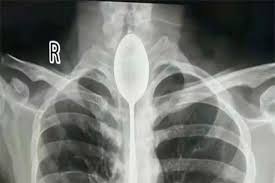

Médicos chinos tuvieron que sacar una cuchara de 20 centímetros que estuvo atorada durante un año en el esófago de...